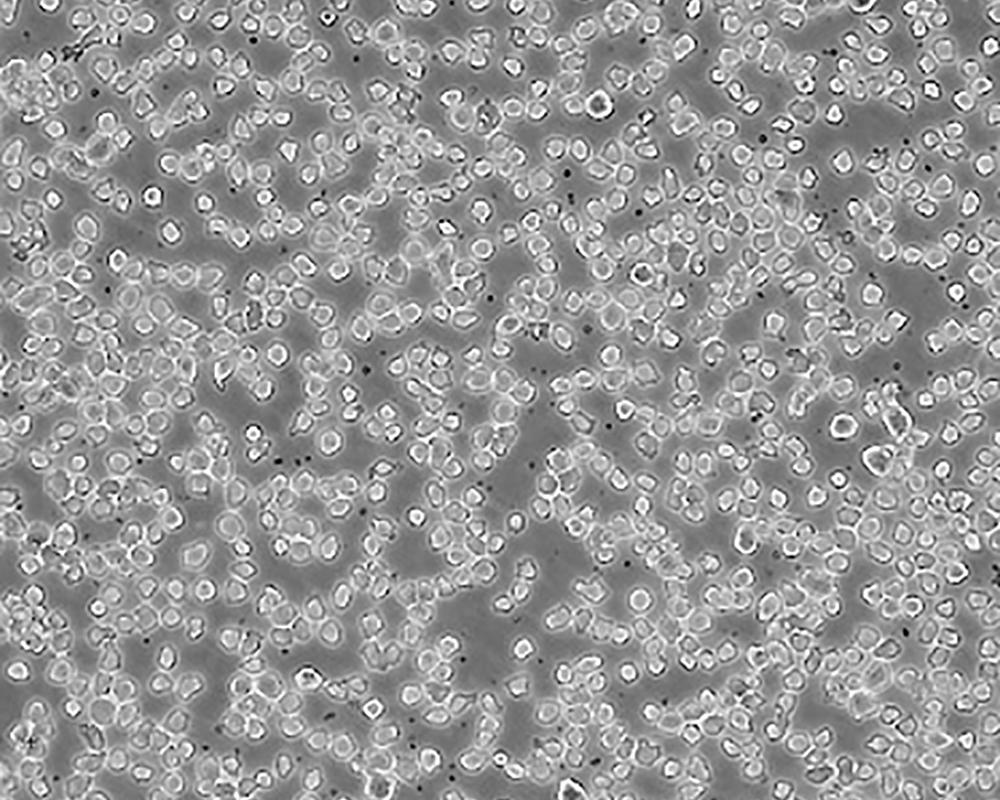

THP-1

產品名稱 THP-1

中文名稱 人單核細胞白血病

組織來源 急性單核細胞白血??;男性

生長特性 suspension

形態(tài)特征 monocyte

細胞描述 該細胞從一名1歲的患有急性單核細胞性白血病的男孩的外周血中分離建立。該細胞可以吞噬乳膠顆粒和激活的紅細胞,細胞膜和胞漿內均沒有免疫球蛋白,表達C3R和FcR;可受佛波酯TPA誘導向單核系方向分化;可作為轉染宿主。